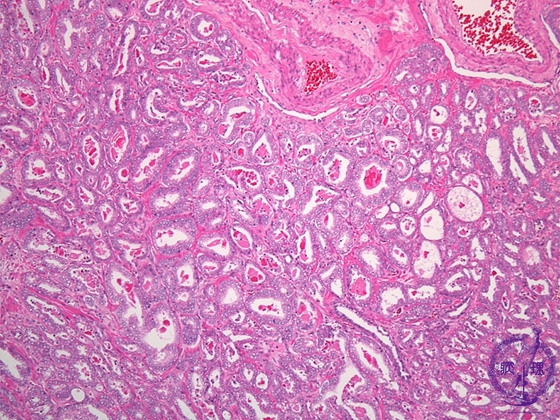

- (2)Prostatic cancer (adenocarcinoma, Gleason grading system)

Histology (HE stain, intermediate power): Well differentiated adenocarcinoma. According to the degrees of tubular structure conservation, the histological degree of differentiation has been classified as well, moderately or poorly differentiated. However, at this juncture, Gleason grading system is common as a means of evaluating prognosis. The Gleason score of this case 6(3+3).